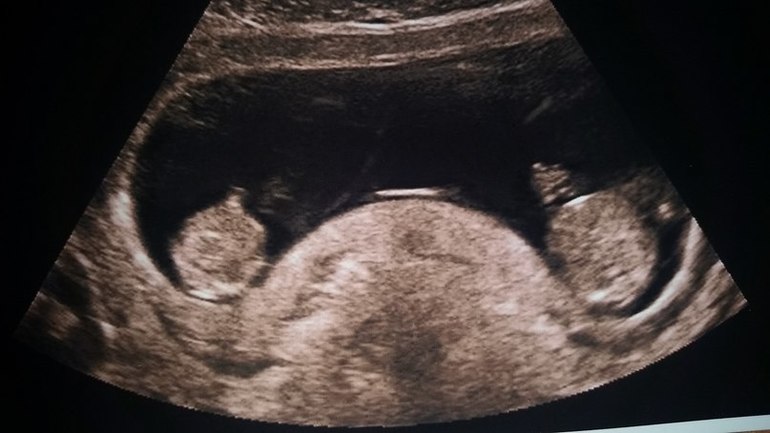

Разумеется, точно пересчитать малышей в вашем животе сможет только врач во время УЗИ (сделать его можно уже на 4–5-й неделе беременности).

Благодаря современным методам диагностики, многоплодная беременность определяется еще на ранних сроках. Во-первых, врач может диагностировать двойню при обычном осмотре – обратив внимание на быстрое увеличение размера матки или услышав двойное сердцебиение. Опытный специалист может диагностировать двойню уже после 4 недель беременности. Во-вторых, двойня диагностируется при УЗИ-осмотре. Обычно это происходит после 12 недель. До этого будущая мать может только предполагать, что носит двойню – например, опираясь на семейную историю и частые случаи рождения близнецов в семье. Анализы крови достоверным способом определить двойню пока не являются.

Однако подтвердить, что у вас будет двойня, сможет только врач. Чаще всего это бывает заметно на УЗИ на 12-й неделе беременности. Если вы недавно узнали о том, что ждете близнецов, рекомендуем прочитать статью c советами при многоплодной беременности.

Иногда на шестой неделе беременности при трансвагинальном УЗИ можно зафиксировать биение сердца (или даже двух!). Тем не менее с какой-либо точностью о присутствии второго ребенка можно будет говорить только после УЗИ на 12-й неделе.

Для диагностики различных состояний, врачи часто используют УЗИ. Будущей маме предстоит регулярно проходить такое обследование. Именно этот метод позволит узнать, сколько малышей находится в матке. Стоит выяснить, когда можно определить двойню по УЗИ. Специалист может увидеть количество эмбрионов примерно в 5-6 недель. Но по разным причинам на маленьком сроке устанавливают, что в матке несколько плодов, не всегда. В ряде случаев врач точно диагностирует этот факт позже, например, во время скрининга в первом триместре.

- УЗИ на сроке 8-12 недель уже может показать присутствие двух или трех плодов. Но на таком сроке ошибка не исключается.

Самый точный способ подтвердить то, что у вас многоплодная беременность — узи диагностика. Этот метод позволяет на ранних сроках определить количество зародышей с точностью 99,3%.

Женщины с многоплодной беременностью должны быть под постоянным присмотром. Определить многоплодную беременность можно на УЗИ, также как при обычной беременности. На сроке в 5 недель на УЗИ можно увидеть, сколько малышей родится.

Многоплодная беременность на раннем сроке

Врач определяет двойню на УЗИ на 5 неделе. Провести исследование можно раньше, когда матка сильно увеличивается. При беременности двойней врачи назначают УЗИ один раз в месяц. Так им видно как развиваются малыши. На 5 неделе не удается определить пол или количество эмбрионов. Это может возникнуть из-за качества УЗИ.